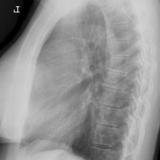

Case 8b Thymoma Lat

Date: 03/27/2009

Views: 14171